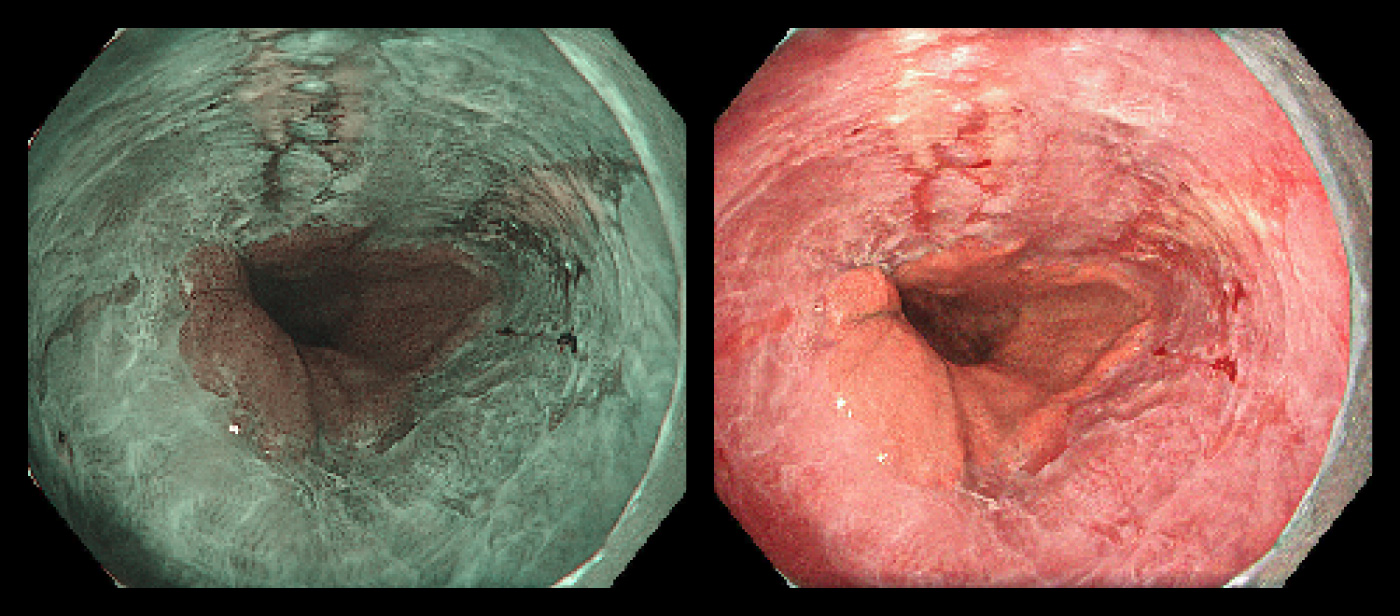

虚血性腸炎

糖尿病や高血圧、喫煙などによる動脈効果の結果、大腸粘膜の血流が減少して、粘膜の炎症が起こり、腹痛や下血を契機に診断されます。下行結腸やS状結腸に好発し、内視鏡では、腸管の縦方向にびらんや潰瘍ができます。

虚血性腸炎 虚血性腸炎